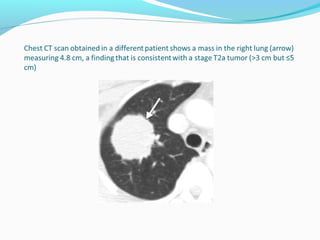

T2 - tumor Greaterthan 3 and smaller than 7 cm Invasion of the visceral pleura Atelectasis or obstructive pneumopathy involving less than the whole lung Tumor involving the main bronchus 2 cm or more distal to the carina.

T2 - tumor

Greater than 3 and smaller than 7 cm

Invasion of the visceral pleura

Atelectasis or obstructive pneumopathy involving less

than the whole lung

Tumor involving the main bronchus 2 cm or more

distal to the carina.